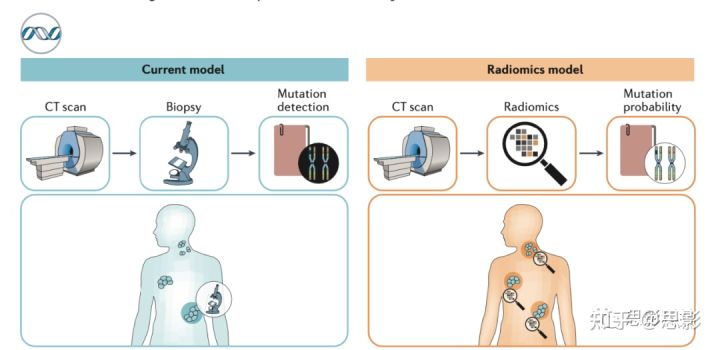

Delta影像组学

已发表的工作主要集中在单个时间点获得的成像数据,主要是在治疗开始前对肿瘤进行成像。Delta radiomics引入了时间成分,包括从治疗过程中获取的图像集中提取定量特征,这提供了关于特征值演变的信息(图5)。Delta影像组学有望改善诊断、预后、预测、监测、基于图像的干预或治疗反应评估。

图5,临床决策支持系统图形用户界面示意图概述

图5说明了delta radiomics的概念。在本例中,临床医生要求基于组合的纵向PET-CT图像对患者进行影像组学分析,这可能有助于改善诊断、早期反应预测、改善临床决策,从而改善预后。